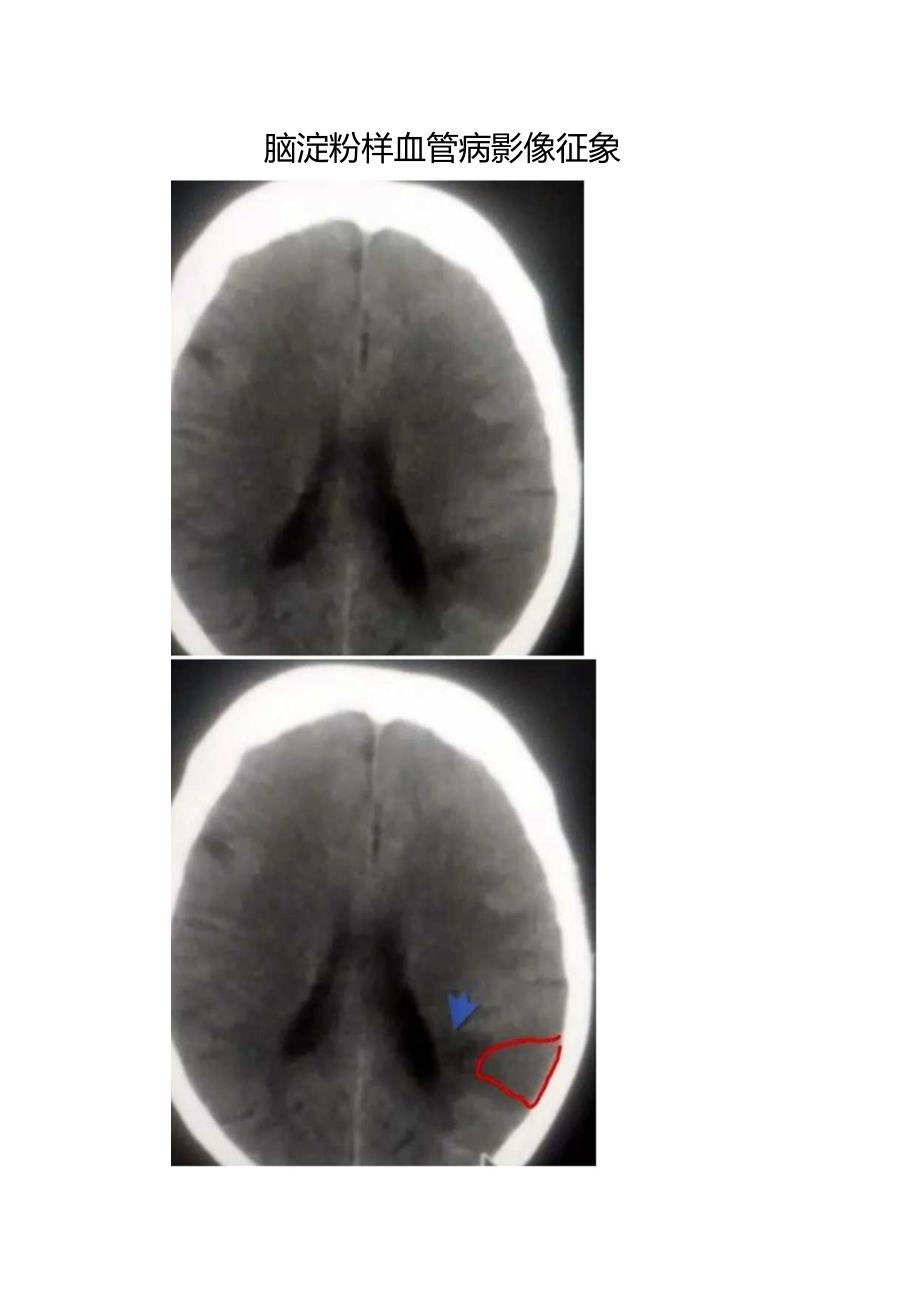

脑淀粉样血管病影像征象